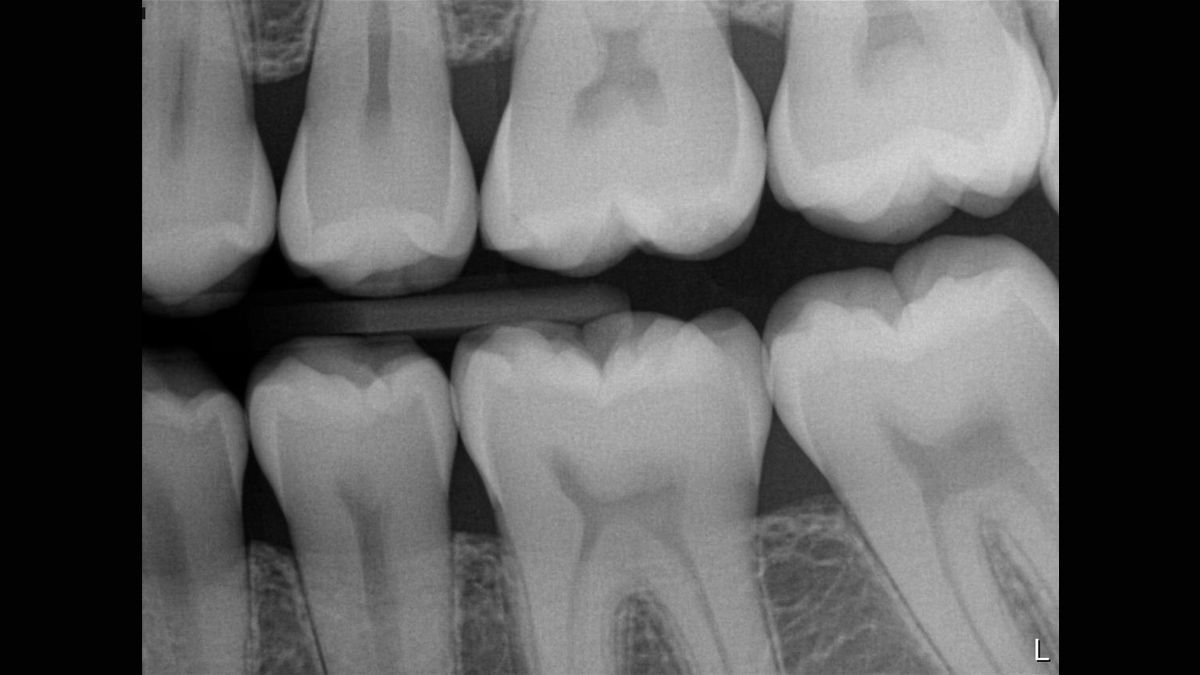

- Doskonała jakość obrazu – teoretyczna rozdzielczość 33 lp/mm (rozmiar piksela 15 μm)

Xios Supreme wyposażony jest w suwak dynamicznego wyostrzania obrazu, co umożliwia dostosowanie ustawień diagnostycznych pod kątem ostrości. Dostępne są również suwaki do modyfikacji jasności oraz kontrastu fotografii. Ustawienia te pozwalają na dostosowanie obrazu odpowiednio do potrzeb prowadzonego leczenia, zwiększając możliwości diagnostyczne oraz usprawniając pracę w gabinecie.

Czujnik posiada funkcję filtrowania z pięcioma dostępnymi opcjami: stomatologia ogólna, endodoncja, periodontologia, odbudowa oraz higiena, które pozwalają na dopasowanie widoku do konkretnej sytuacji klinicznej.